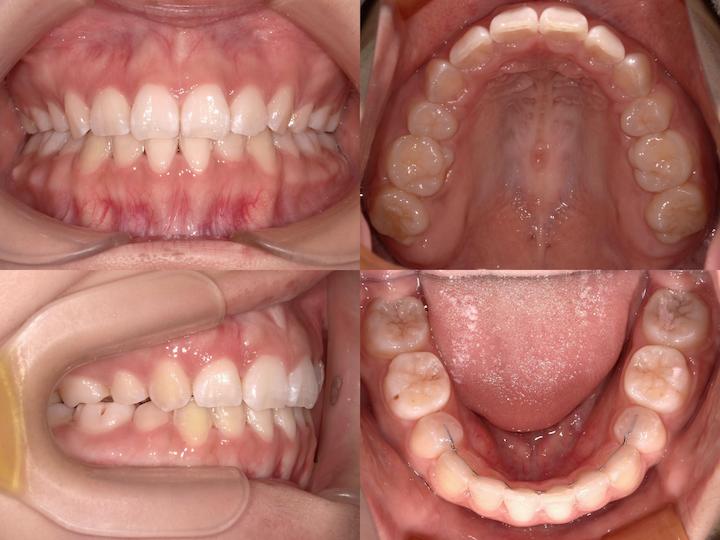

反対咬合のハーフリンガル矯正

Before

After

治療期間: 1年8カ月

前歯の反対咬合と下顎骨の右側偏位を、左下4番抜歯を伴うハーフリンガルで治療しました。

初診時年齢3110ヶ月の患者様です。前歯の反対咬合と下顎骨の右側偏位に対し、左下4番目の歯を抜いてスペースをつくった後、下の前歯を左後方に移動しました。上の歯は裏側に、下の歯には表側に矯正装置をつけるハーフリンガル矯正を行いました。治療後は反対咬合も改善され、噛み合わせたときに上の前歯が下の前歯よりも前にくるようになりました。また、上下の歯の中心も合わせることができました。

反対咬合を改善させる過程では、前歯の干渉により、咬合性外傷(噛み合わせの力が強いことによって歯や歯周組織、顎関節などを損傷すること)を生じるリスクがあります。そのため、こちらの症例では奥歯の高さを調整することで前歯の当たりを調整しながら治療を進めました。